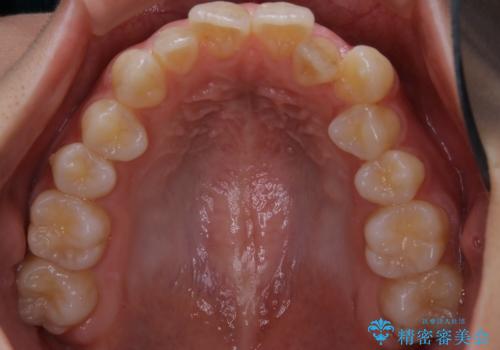

- 前歯の歯並びの改善を希望され来院された患者様です。

初診時の歯並びの状態としては、上下ともに全体に及ぶの中等度のがたつき(叢生)があり、全特に左上の前歯は1本だけ引っ込んでいる状態でした。

抜歯は行わず上顎の奥のスペースを利用して歯をスライドする方法の他に歯列弓の拡大やディスキング(歯と歯の間の隙間を作る処置)を行い叢生を改善しました。

歯の大きさの不揃いが原因の正中のズレは、ディスキング量を調整することで合わせています。